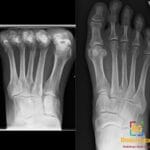

- Radiology Cases: Images with a to-the-point discussion highlighting the specific diagnostic criteria.

- Radiology Case of the Day Collection: Aunt-Minnie Board Cases for Rapid Review.

- Radiology Spotters: 700+ spot / “Aunt-Minnie” cases divided into sets of 10 each!